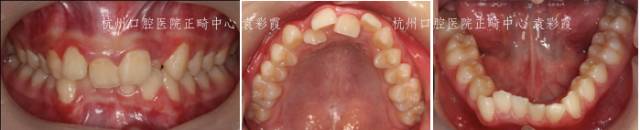

深覆合治疗前

戴上牙套

脸型变化——正面

脸型变化——侧面